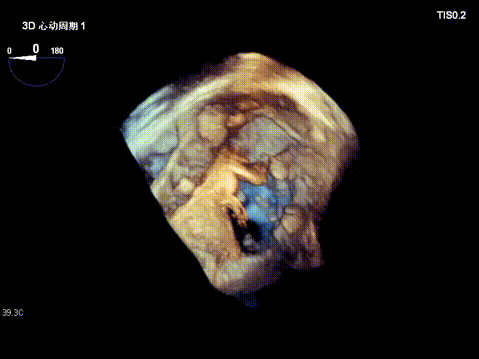

Surgical Outcome

1. Regurgitation Effect: Reduced from massive (5+) to moderate (2+).

2. Annuloplasty Effect:

Ultimately, the tricuspid annulus was significantly reduced, and regurgitation was downgraded from critical to mild‑to‑moderate.